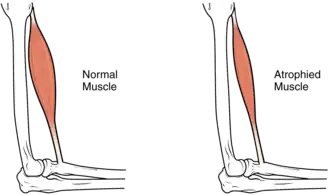

| The size of the muscle is reduced, as a consequence there is a loss of strength and mobility. | |

Muscle atrophy is the loss of skeletal muscle mass. It can be caused by immobility, aging, malnutrition, medications, or a wide range of injuries or diseases that impact the musculoskeletal or nervous system. Muscle atrophy leads to muscle weakness and causes disability.

The hallmark sign of muscle atrophy is loss of lean muscle mass. This change may be difficult to detect due to obesity, changes in fat mass or edema. Changes in weight, limb or waist circumference are not reliable indicators of muscle mass changes.[1]